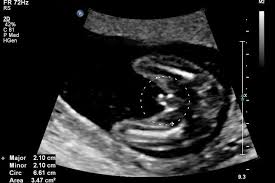

At 18 weeks your baby to be is large enough that your sonographer will perform the ultrasound transabdominally. In the lungs the smallest tubes bronchioles start to develop at the tips of the branches. She looks more like a tiny human each day. Your baby s ears are now in their final position although they re still standing out from his head a bit.

Your baby is about 14 2cm 5 6in from head to bottom crown to rump almost the size of a bell pepper and weighs up to 190g 6 7oz hill 2019. The brain has been developing rapidly. So your baby s overall rate of growth is as important as the actual size. See how your baby is developing at 18 weeks of pregnancy.

With a transabdominal exam the sonographer will first place gel on your abdomen so.